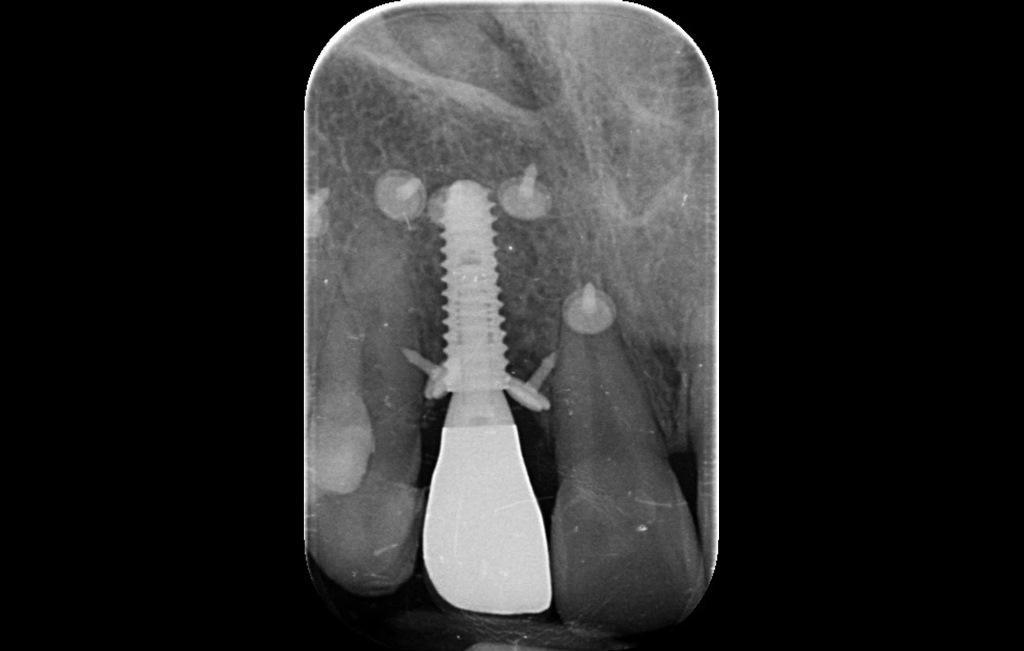

Периапикальные рентгенограммы показали контакт кости с мезиальной и дистальной сторонами имплантата. Однако клиническое исследование и КЛКТ выявили потерю лабиальной и небной костной массы, что свидетельствует о неправильном расположении имплантата (фото 2).

Фото 2: КЛКТ свидетельствует о неправильном расположении лабиального имплантата и потере костной массы.